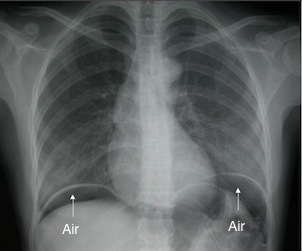

La radiographie de l’abdomen sans préparation reste surtout indispensable pour éliminer un pneumopéritoine par perforation d'un ulcère sous la forme d'un croissant gazeux sous-diaphragmatique (Figure n°1).

Figure n°1 et 2 : Pneumopéritoine sur un ASP de face et sur une tomodensitométrie.

La tomodensitométrie (TDM) abdominale permet de confirmer le pneumopéritoine devant la présence d'air dans le péritoine et peut orienter la localisation de la perforation.

Il est interdit de réaliser dans ce contexte une endoscopie car cet examen ne fera qu'aggraver le pneumopéritoine en introduisant encore plus d'air. Le seul traitement est alors la chirurgie en urgence.